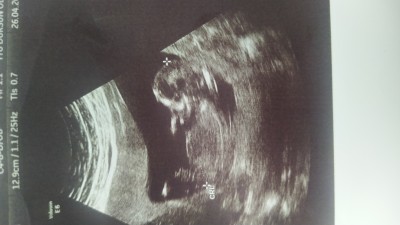

Cinsiyettt tahmini verir misiniz

Sizce cinsiyeti New kizlar

Fotoğraf 13 haftalıkken suan16+2

%50 kiz %50 erkek.

Erkek canım, benim oğlum da öyle görünüyordu, Rabbim gönlüne göre versin inşallah

Bende kiz diorum sen kiz ve erkek icin alisverise basla sonucta tahminlerde bulunduk senin icin

Benim ki de aynı böyleydi erkek doğdu canim